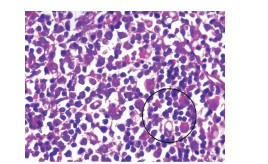

Primary hepatic lymphoma with anemia and hypoproteinemia: A case report

Weifeng LI, Fan WU

2021, 37(8): 1911-1913. DOI: 10.3969/j.issn.1001-5256.2021.08.034

Abstract(937) HTML (226) PDF (2390KB)(46)

Abstract: